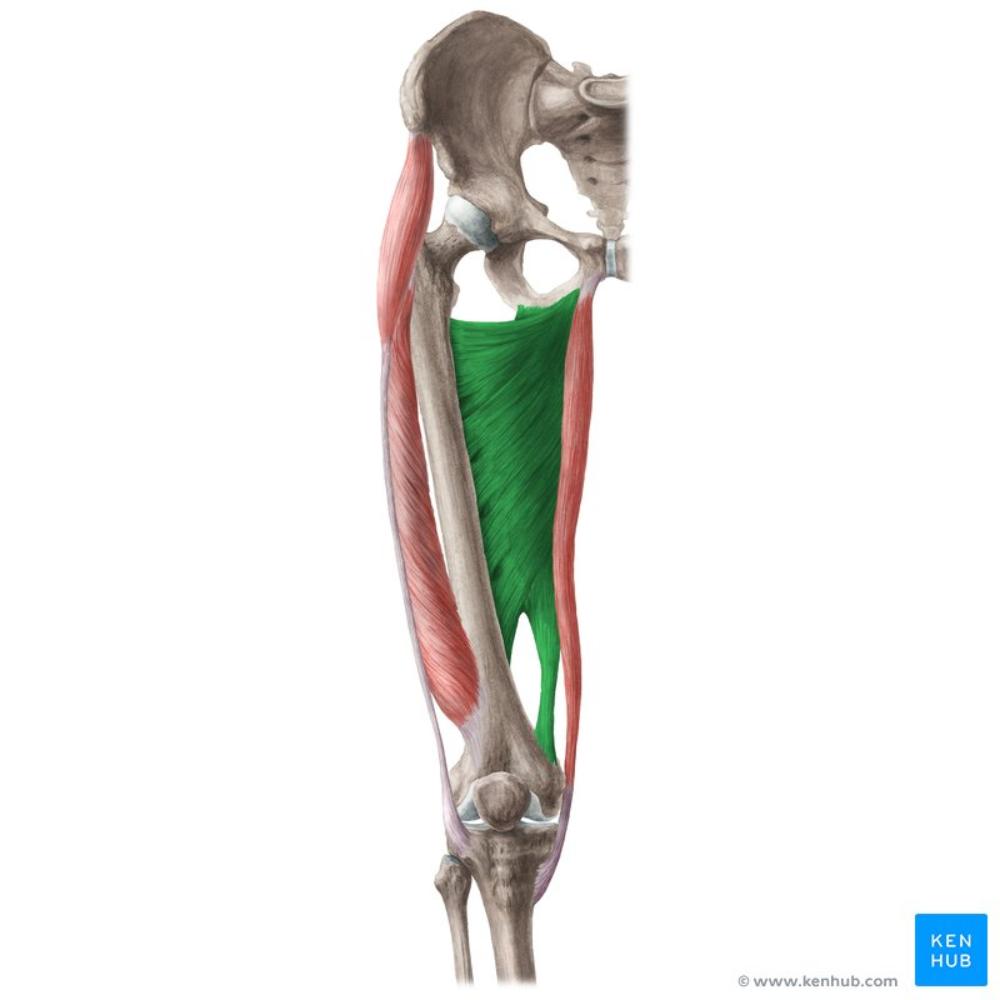

adductor magnus

O: inferior ramus of pubis

I: linea aspera, adductor tubercle of femur

A: adducts and extends thigh

N: obturator nerve